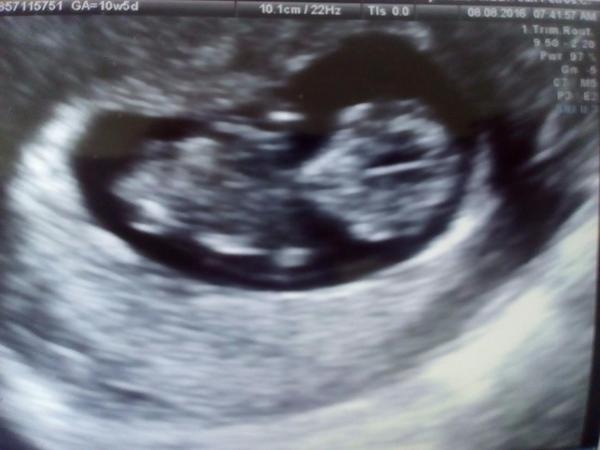

Hlasim, ze kontrola dopadla dobre :D vse je jak ma. Nervy jak u maturity. Pritel se sel taky podivat. Uz jsem videla rucicky a nozicky. Je to zas o necem jinem nez minule ten mimoňek 🙂 za 14dni screening